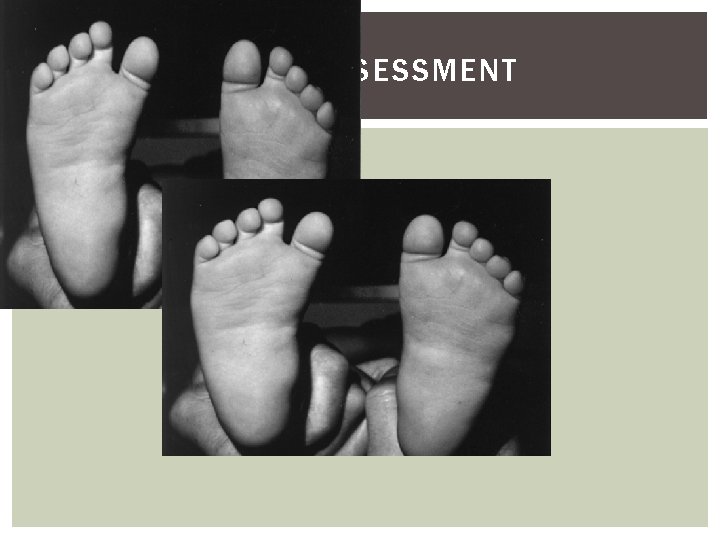

FOOT - ASSESSMENT

CALCANEOVALGUS V’S CVT